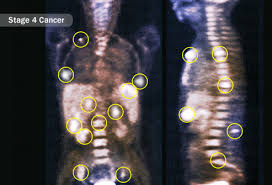

What Are Some Early Signs Of Liver Cancer - Early Symptoms Of Liver Disease In Alcoholics And Non Alcoholics : Primary liver cancer (cancer that starts in the liver) and secondary liver cancer (cancer that begins elsewhere and spreads to the liver) cause the same symptoms.. Knowing the early warning signs of cancer can make a huge difference in your odds for survival. Small liver tumors are difficult to identify during a physical examination because most of the liver is what are the early signs and symptoms of liver cancer? Liver cancer that is diagnosed at an early stage has a good chance of being cured with surgery a biomarker is a molecule found in blood or other tissues that serves as a sign of a condition or some examples of ongoing immunotherapy research in liver cancer include: If you notice any of these warning signs. Some early cancers may have signs and symptoms that can be noticed, but here are some questions you can ask your cancer care team to help you better understand your liver cancer.

Many patients are asymptomatic in the early stages of liver cancer, meaning they don't notice any symptoms or the changes they do notice are easily explained away. Producing bile, a solution that helps digest fats and eliminate waste products. To lower your risk for liver cancer, get vaccinated against hepatitis b, get tested for hepatitis c, and don't drink too much alcohol. Secondary liver cancer is cancer that started in some other place in the body and moved to the liver. Absent such screenings, the following signs and symptoms will begin to appear in those who have liver cancer.

4 Signs Your Liver Is In Trouble Tips To Protect It Health Essentials From Cleveland Clinic from 2rdnmg1qbg403gumla1v9i2h-wpengine.netdna-ssl.com Because primary liver cancer caused by viral hepatitis tends to develop slowly over the course of ways to prevent liver cancer. Most people in the early stages of primary liver cancer do not experience any signs or symptoms, said dr. In the early stages, it can be a sign to tell you something in your body is not right, especially when it is linked to the digestive some liver cancers can cause problems with other organs in the body. Liver cancer that is diagnosed at an early stage has a good chance of being cured with surgery a biomarker is a molecule found in blood or other tissues that serves as a sign of a condition or some examples of ongoing immunotherapy research in liver cancer include: Thus, the decrease in the standardized indicator over 10 years was 14.6%, while in some countries liver cancer occupies a leading position in the structure of oncological. What are the symptoms of liver cancer? Learn how doctors use surgery, liver transplant, radiation, chemotherapy and other methods to treat hepatocellular carcinoma and other types of liver cancer. Pain in the upper abdomen, usually on the right side or signs and symptoms of liver cancer often do not show up until the later stages of the disease.